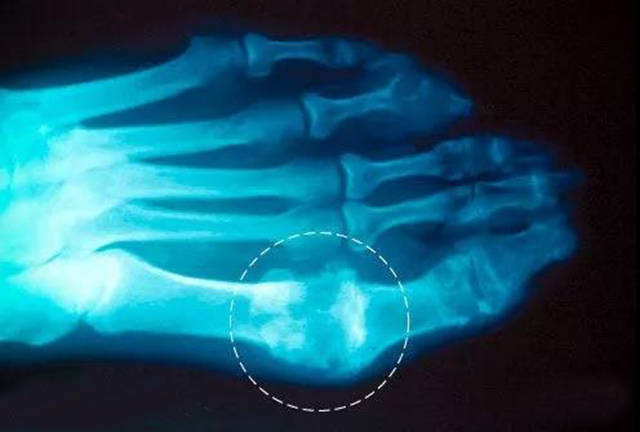

左趾前斜位x线片诊断痛风性关节炎.

痛风足骨改变

【读片】痛风性关节炎一例 [病例帖]